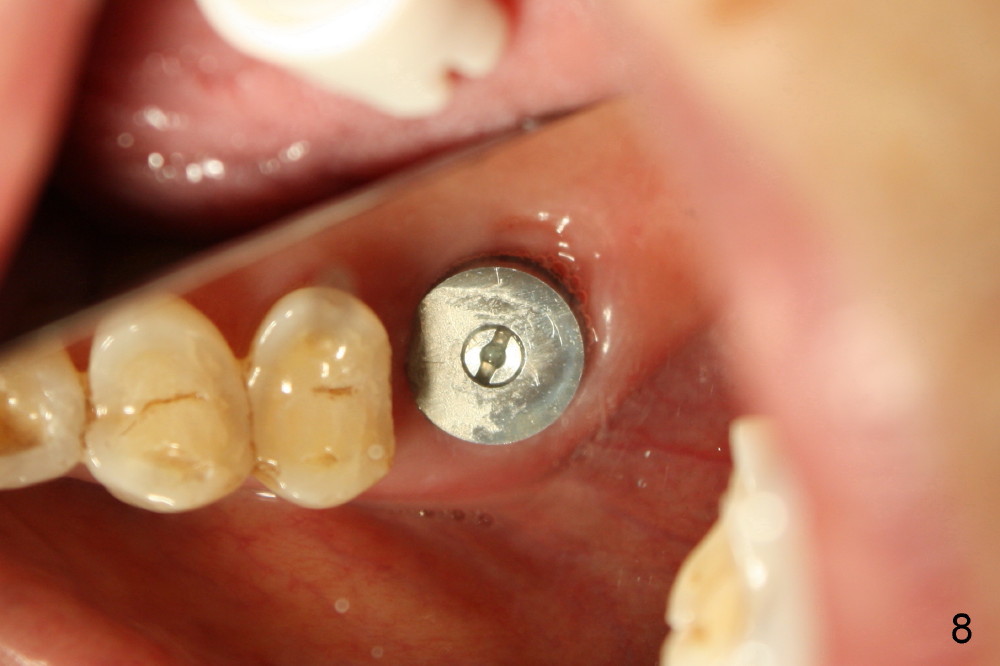

Extraction turns out to be simple with sectioning. After debridment of the socket and soaked with Clindamycin, the ostoeotomy forms using osteotomes, followed by insertion of a tap (Fig.4 T, 6x14 mm). After adjustment of the trajectory (Fig.4 arrow), larger taps are used (7x14, 8x14 mm) before placement of a 8x14 mm implant (Fig.5 I). There is small gap (Fig.6 arrowheads) around the implant. The wound is protected by perio dressing (Fig.7). The dressing is removed 7 days postop. Fig. 8 taken 2 weeks postop shows that the peri-implant gap has closed.